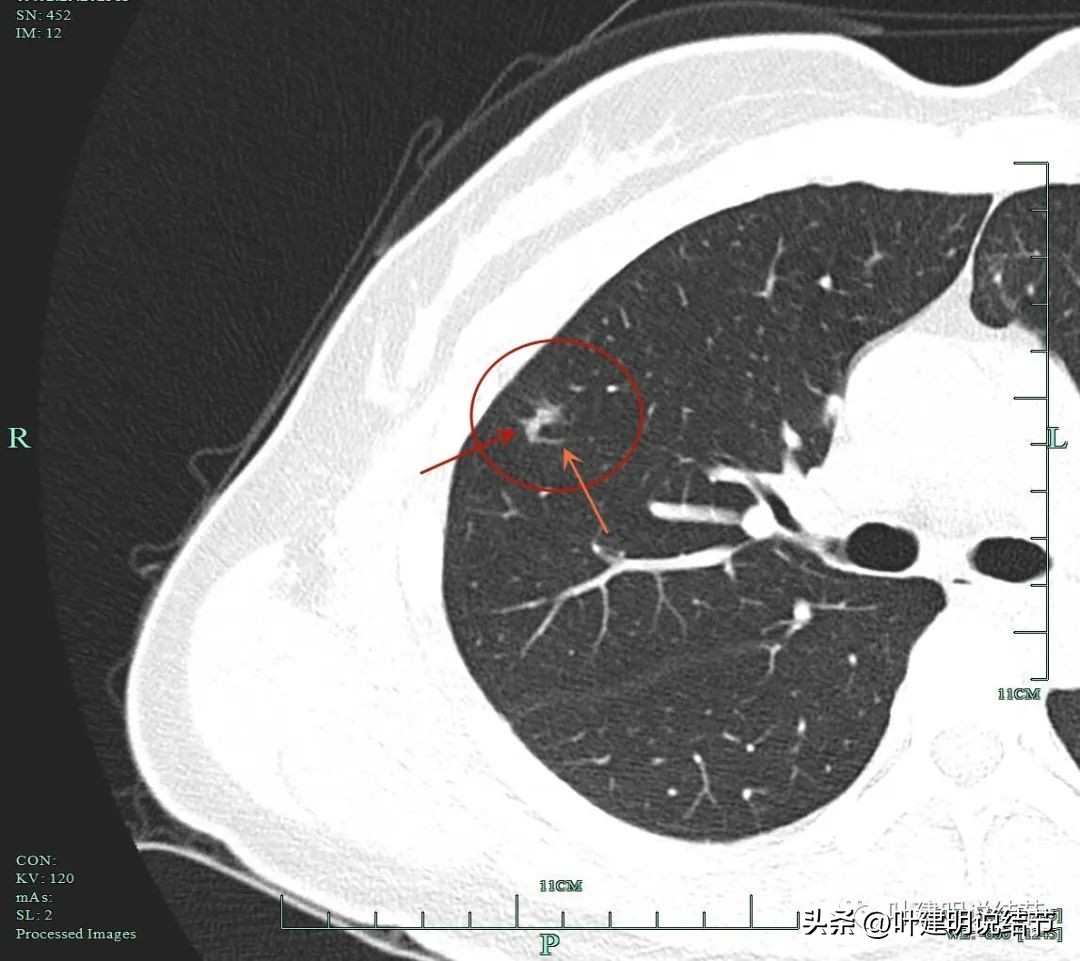

非薄层图像:

病灶1:右上叶淡磨玻璃结节,边缘较糊,似有微小血管走向病灶。

病灶2:右上叶混合磨玻璃结节,边缘毛糙,中间有空泡征,邻近有微小血管走向病灶。

病灶3:右下叶近叶裂处微小磨玻璃结节,偏长条状,有微血管进入。